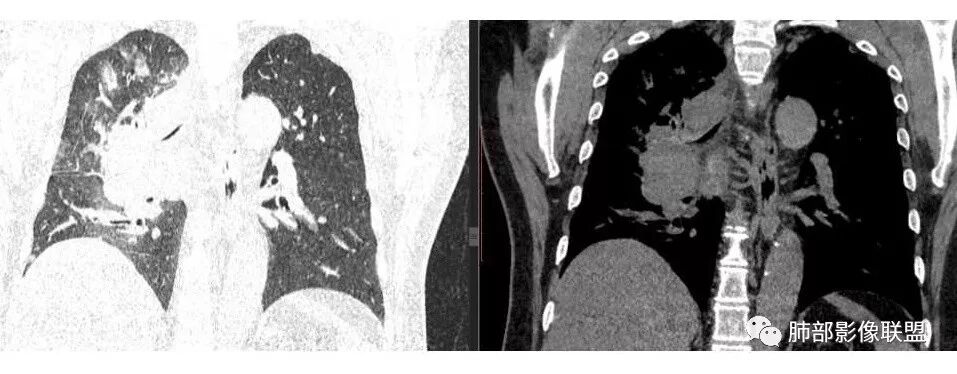

1.右肺上叶不规则结节影,右肺门及纵隔多结节并形成巨大块影,密度均匀,沿途支气管明显狭窄。

原发灶小或隐匿,肺门纵隔淋巴结异常增大,所谓“娘小崽大”常见于肺小细胞癌!

2.右肺小叶间隔增厚伴微小结节,提示癌性淋巴管炎。

肺门及纵隔多发淋巴结。2L,4R,3区都有肿大淋巴结。